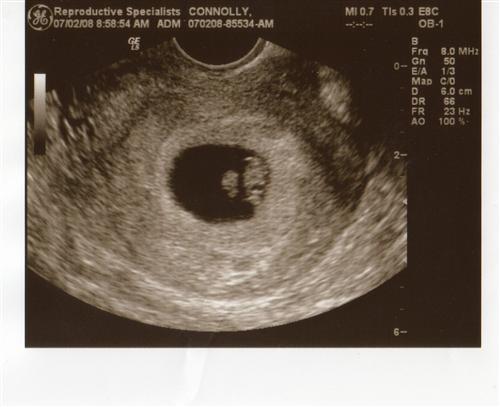

Hey girls jut thought i would share we got to see our baby again at our doc appt. i am 7w4d and babys heart beat went up from 119 to 146 YIPPE. He/She grew so much in 1 week. To me looks like a penguin.. i cant tell which is the head or tail. Thanks for letting me share. I cant wait till next week already! If the insert doesn't come up pics are in my album.